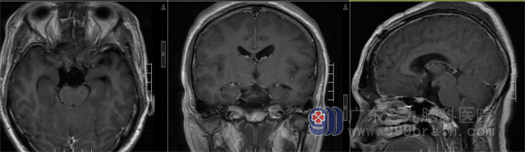

我院神经外一科主任张良接诊后,仔细查看了患者的影像资料,患者的肿瘤位于鞍区,且最长直径超过5厘米。结合患者的症状,初步诊断患者为颅咽管瘤。

▲术前影像检查:鞍上-三脑室区示一范围约41mm×34mm×52mm的囊状各序列高信号影为主异常信号。

▲术后复查,肿瘤全切

完善相关检查,征得患者及家属同意后,张良团队在全麻下为患者实施肿瘤切除术。手术顺利,术后复查肿瘤全切,病理提示是造釉细胞型颅咽管瘤,CNS WHO 1级。